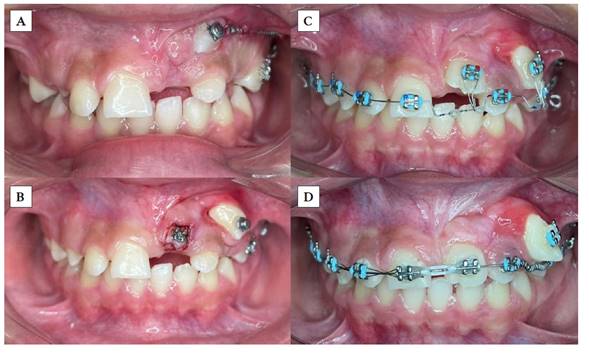

Inicialmente, se realizó la exodoncia del canino primario superior izquierdo para mejorar el corredor de erupción del incisivo central superior permanente. En la fase de ortodoncia inicial se coloca la aparatología fija con prescripción de Roth slot 0,22, exclusivamente en las UD 24, 25 y 26, además de un minitornillo como anclaje absoluto en la zona molar izquierda para tracción distal del canino superior (UD 23) y evitar así mesializaciones no deseadas al consolidar dicho sector. Al ubicar la UD 23 en su posición correcta, la UD 21 erupcionó posterior a destrabar ese espacio. Después de observar que dicha unidad dentaria iba erupcionando, se realizó un ojal quirúrgico y se cementó un bracket en la UD 21 y en el resto de la arcada superior para continuar con los pasos de alineación y nivelación, siguiendo la secuencia de arcos con normalidad en la ortodoncia correctiva (Figuras 4 y 5).

Al tener los dientes en su correcta disposición, se apreció que el paciente presentaba una topografía gingival asimétrica, por lo que se procedió a realizar gingivectomía y gingivoplastia del sector anterosuperior para obtener un contorno más estético y fisiológico del tejido blando (Figura 6). Siguiendo un orden, se observa un exceso de encía queratinizada en algunas unidades dentarias; por ejemplo, en la UD 23 se identifica una banda muy estrecha. Además, es necesario realizar ajustes en la estética dental para armonizar la anatomía dentaria, lo cual también repercute en la evaluación de los parámetros estéticos.

El caso no está terminado, aún se aprecia asimetría a nivel del contorno gingival, pero se espera la evolución del tratamiento ortodóntico para realizar un solo procedimiento gingival acorde a la necesidad de cada zona. El próximo paso es culminar con ortodoncia correctiva convencional, haciendo cementado de aparatología inferior, con secuencia de arcos hasta finalizar con retiro y retención. Por motivos económicos, el paciente no ha concluido todas las fases del tratamiento. El problema estético fue el que hizo que la madre buscara ayuda. Se plantea la finalización superior exclusivamente debido a que los parámetros oclusales primordiales están presentes: clase I molares y caninas, líneas medias, contactos interdentales firmes, sin espacios e inclinaciones dentarias aceptables.